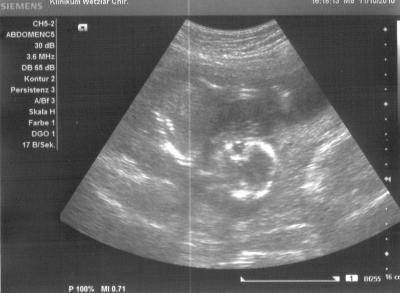

...und ich hab echt nen wilden kleinen Turner! Hier mal ein Foto, wo es gerade einen Purzelbaum schlägt, hihi... War total schön den kleinen Spatz wieder zusehen, und mein Mann und ich meinen auch gesehen zu haben, dass wir einen kleinen Jungen bekommen! Da wir aber beide keine Gynäkologen sind und das US-Gerät auch nicht dafür gemacht ist, bleibt es erstmal bei der Vermutung, und wir schauen mal, ob der FA nächste Woche mehr sieht!

Bild zu Hab gestern auch wieder meinen kleinen Schatz bewundern können... - Forum für März - Mamis